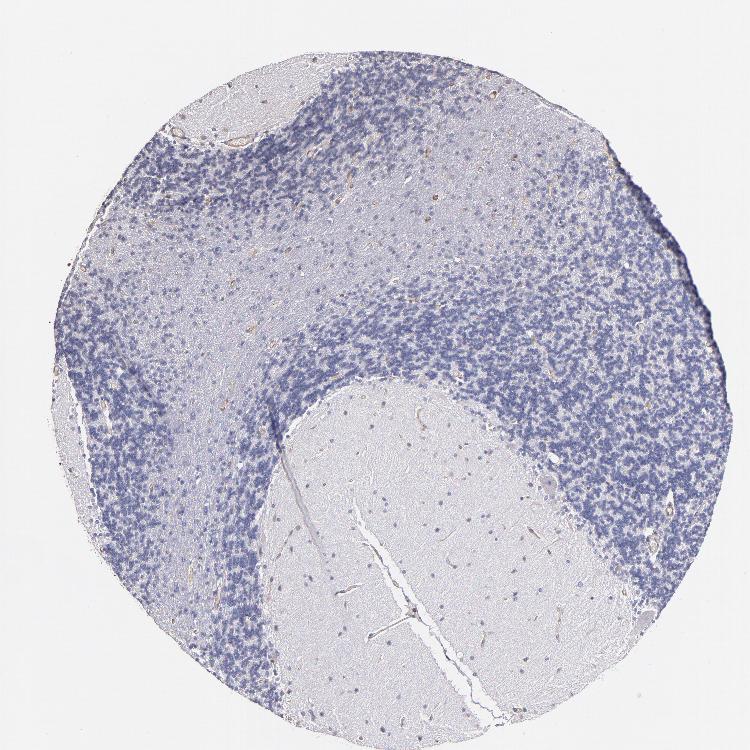

CEREBELLUM - Antibody stainingi

Antibody staining in the annotated cell types in the current human tissue is reported as not detected, low, medium, or high, based on conventional immunohistochemistry profiling in selected tissues. This score is based on the combination of the staining intensity and fraction of stained cells.

Each image is clickable and will lead to virtual microscopy that enables deeper exploration of all samples and also displays staining intensity scores, fraction scores and subcellular localization as well as patient and tissue information for each sample.

Antibody HPA002380

Purkinje cells Not detected

Cells in granular layer Not detected

Cells in molecular layer Not detected